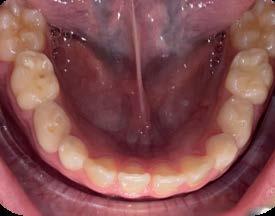

Sobremordida vertical excesiva en paciente pediátrico. Caso clínico

Estudio comparativo de la precisión entre 2 distintas técnicas

Las restauraciones indirectas son el día a día de la odontología, por lo tanto es de suma importancia conocer los diferentes sistemas para tomar impresiones dentales, ya sea convencionales o modelos digitales. Objetivo: comparar la precisión de la toma de impresión convencional con polivinil siloxano (Elite P&P) vs. el uso de una técnica de escanéo digital. Metodología: estudio transversal, comparativo, observacional e in vitro. En un tipodonto Nissin se realizó una serie de señalizaciones las cuales se fijan con cianocrilato para posteriormente tomar una impresión convencional, se fijan los vástagos con patern resin en la impresión y se vacía con yeso tipo IV de Zhermack, después se realizó un escaneo digital al tipodonto para así comparar

las distancias entre los diversos puntos marcados, esto con un vernier eléctrico. Resultados: se obtuvieron resultados ligeramente significativos entre las 2 distintas formas de obtener un modelo de trabajo. Conclusión: Según los hallazgos encontrados en este estudio, se determinaron las siguientes conclusiones: es de suma importancia utilizar los materiales como lo marca el fabricante. Los resultados obtenidos requieren estudios más precisos, pero pudimos determinar que los tiempos de trabajo son menores con la técnica digital, y por ende requiere menor ajuste.